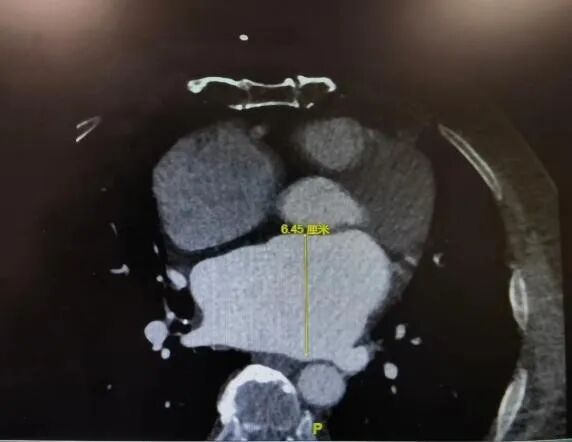

手术直播(十八):经心尖TAVR

今日下午的第三台手术直播来自广东省人民医院心外科郭惠明教授与刘健教授手术团队。患者为76岁男性,反复胸闷伴气促1年、加重2周,强心、利尿治疗效果有限,高血压病史20年。

经胸心脏彩超示:主动脉瓣重度返流,缩流颈8.5mm,返流面积8.1cm²;左心扩大,左室舒张末内径66mm,左室收缩末内径40mm,左房45mm,EF62%。基于心脏CTA的评估显示患者为三叶主动脉瓣且无明显钙化,瓣环周长折算直径24.4mm,左冠开口高度9.8mm,左冠瓣瓣叶长度13.5mm,左髂总动脉瘤。NT-proBNP1991.0pg/ml,肌酐174.57umol/L。心电图、肺通气功能、胸片未见异常。

该患者体表面积为1.86m²,STS PROM达8.68%。鉴于患者瓣为纯返流病变,且年龄较高、左冠瓣较长、手术风险大,在与患者及家属充分沟通后,郭惠明教授与刘健教授决定给患者行经心尖TAVR,选用27mm瓣膜。

经DSA透视下定位心尖位置,主刀团队于左腋前线第五肋间做一3.5cm水平切口,从穿刺心尖至退出植入系统、荷包打结仅耗时不到10分钟,整台手术耗时仅56分钟,再次造影及复做经食道心超见瓣膜位置满意,无明显瓣周漏及瓣内返流、左右冠脉显影良好,心尖切口荷包无出血,在做到微创、高效的同时,实现了满意的手术效果。